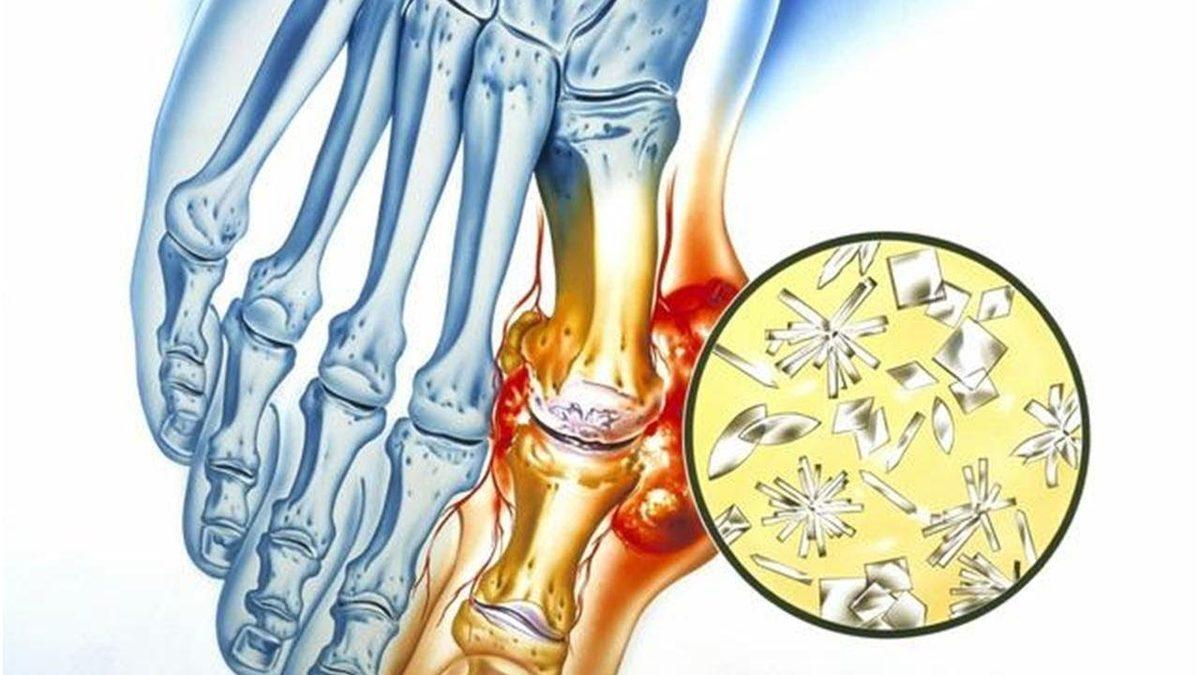

Gut hastalığı en geniş tanımıyla bir eklem iltihabı hastalığıdır. Genel olarak fazla protein alımı sonrası kana karışan ürik asit birikir ve dışarı atılamaz. Dışarı atılmayan ürik asit ayak başparmağı başta olmak üzere diğer ayak eklemlerinde kristalleşerek ağrı ve hassasiyete neden olan bir iltihap oluşturur.

Gut atağının çoğu zaman ilk ortaya çıktığı yer ayak başparmağı eklemidir. Ayak bileği, diz ve ilerleyen zamanlarda omurga sisteminde bile iltihap oluşturabilir. Gut atağı her zaman eklemlerde meydana gelir çünkü ürik asit gece kan sıcaklığı azalınca eklemlerde toplanarak kristalize bir hal alır.

Proteinin parçalanması ile ürik asit açığa çıkar ve kana karışır. Böbrek bu kandaki ürik asidi süzer ve idrar yoluyla dışarı atar. Eğer vücutta olması gerektiğinden çok daha fazla ürik asit varsa ya da böbrek sorunu yaşanıyorsa ürik asit dışarı atılamaz ve gut hastalığına neden olur.